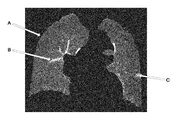

• FIG. 13 is an exemplary figure representing the results of the existing lung segmentation processing for the chest image acquired by MRI apparatus.

• the data of chest wall tissue is still left in the area of the extracted lung image pointed by arrow A after refining.

• the thin vessels could be included, but the relatively thick vessels cannot be correctly included, as shown in the area pointed by arrow B, meanwhile, the nodules area as pointed by arrow C cannot be included as well.

FIG. 13 is an exemplary figure representing the results of the existing lung segmentation processing for the chest image acquired by MRI apparatus. As shown in FIG. 13, the data of chest wall tissue is still left in the area of the extracted lung image pointed by arrow A after refining. On the other hand, the thin vessels could be included, but the relatively thick vessels cannot be correctly included, as shown in the area pointed by arrow B, meanwhile, the nodules area as pointed by arrow C cannot be included as well.